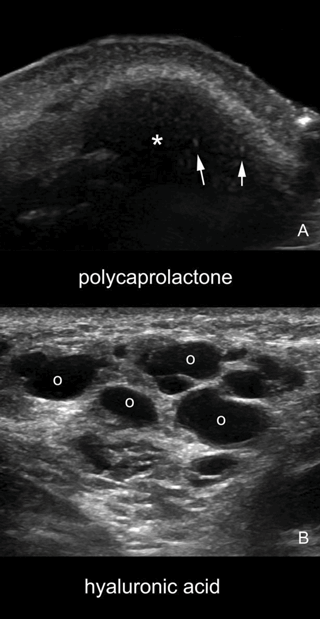

Figure 1: A comparison sonogram between PCL and HA. The HA produces multiple anechoic pseudocystic structures (B). The bright hyperechoic spots noticed in PCL represent microspheres with collagen stimulating properties (A).

This product is composed of microspheres of a totally bioresorbable polymer, polycaprolactone (PCL) (30%), and is in an aqueous carboxymethyl cellulose (CMC) (70%) gel carrier.

The CMC gel carrier has an immediate volumising effect and is gradually resorbed by macrophages in six to eight weeks, the PCL microspheres stimulate neocollagenesis. Rhinoplasty surgery, if necessary is planned for three months after the treatment. It is the authors’ impression that following PCL injections, the nasal soft tissue envelope is more resistant during surgery.